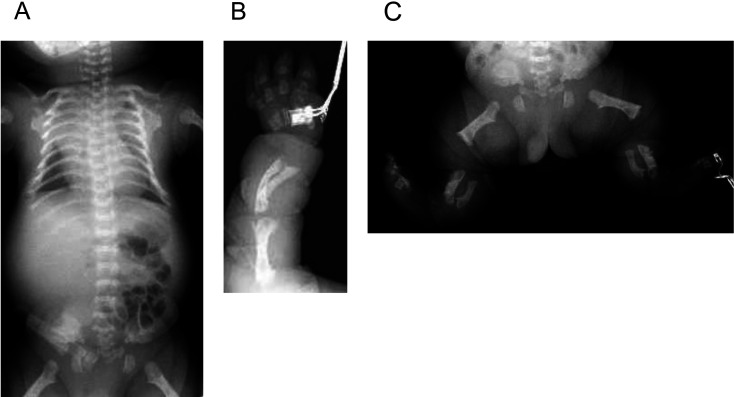

Severe achondroplasia with developmental delay and acanthosis nigricans (SADDAN) is a bone dysplasia caused by a pathogenic variant of fibroblast growth factor receptor 3 (FGFR3). Pathogenic variants in FGFR3 also cause thanatophoric dysplasia (TD) and achondroplasia. Although the findings of SADDAN and TD during the fetal and neonatal periods are similar, they differ in their long-term prognoses. We conducted FGFR3 analysis in one male patient because of the difficulty in differentiating SADDAN from TD during the neonatal period. We found that the patient had a pathogenic variant, p. Lys650Met, which was similar to that previously reported in patients with SADDAN. Reports on long-term survival in patient with SADDAN are scarce, and there have been no reports of treatment with GH. We administered GH therapy for a markedly short stature. After treatment, his height increased by 4 cm each year for 4 years, the frequency of hospitalizations due to respiratory failure decreased, and the health improved. FGFR3 analysis is useful for diagnosing SADDAN during the early neonatal period. GH therapy may have contributed to the patient's long-term survival.

Abstract Image